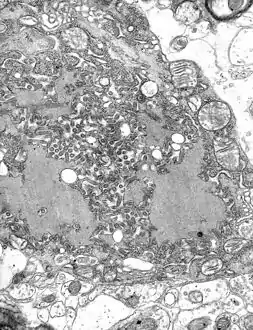

![]() مجهر إلكتروني نافذ صورة مجهرية with numerous rabies فيروسs (small dark-grey rod-like particles) and Negri bodies (the larger علم تشخيص الأمراض cellular inclusions of rabies infection) | |

تحدث جميع أحداث النسخ والتكرار في السيتوبلازم داخل "مصنع الفيروس" المتخصص، أو الجسم النيجري (سُمي على شخص يدعى أديلتشي نيجري [الإنجليزية][5]). و يبلغ قطرها 2-10 ميكرون وهي تعتبر نموذجًا لعدوى داء الكلب، لذلك اُستخدمت كدليل هيستولوجي لمثل هذه العدوى.[6]